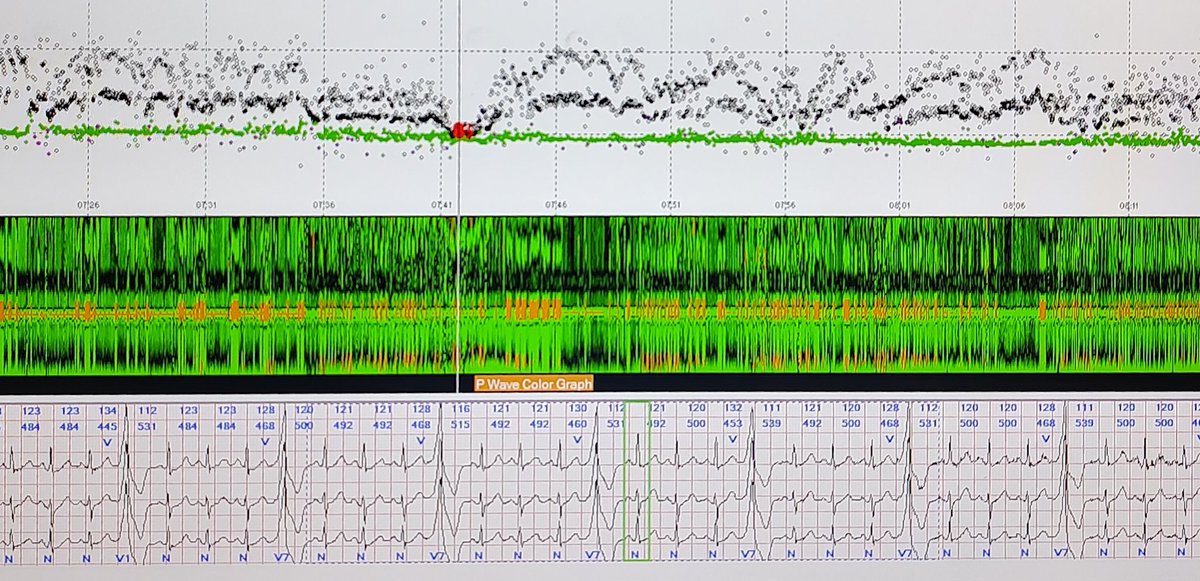

Fixed coupling interval of VEs about 460 msec as green line. When sinus accelerates (the second pic) VEs come at about the rate of P waves. Sometimes VEs may start inadvertently from P wave and mimic intermittent WPW. But longer recording reveals there's no preexcitation.